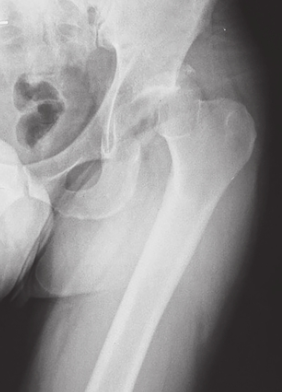

患者1周前于车祸中受伤,受伤时患者位于副驾驶座位,所坐车辆与前车追尾。车辆发生撞击后,患者出现左髋部畸形、剧烈疼痛及活动障碍。外院影像学检查诊断为左髋关节脱位、左髋臼骨折、左股骨头骨折(图4~图6)。

图4伤后X线片示左髋关节脱位,股骨头骨折